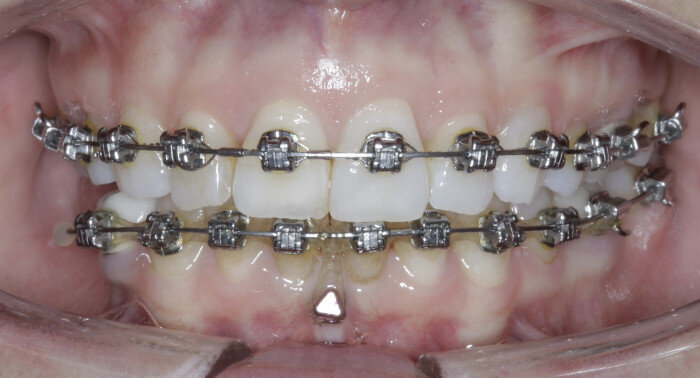

Case 4: Mandibular distalisation

A great solution for Class III patients in need of mandibular distalisation for profile aesthetics and dental function is buccal shelf TADs. This solution allows for noncompliance correction of Class III cases with decreased compensation of the maxillary arch (Figs. 42–45, beginning of treatment). For these cases, a 2 × 12 mm Ortho Bone Screw is placed mesial to teeth #47 and #37 into the buccal shelf of the mandibular body. If the patient has mandibular third molars, then they are extracted right before the TADs are placed once in the stainless-steel wires.

Once the patient has progressed to stainless-steel wires, buccal shelf TADs are placed. A mandibular pre-posted stainless-steel wire is used, and a VectorTAS NiTi closing spring is placed from the buccal shelf TAD to the post (Fig. 46). Once the Class III has been corrected, a steel ligature is used to retain the Class III malocclusion while finishing and detailing are completed (Figs. 47–51, end of treatment).

Fig. 42

Fig. 43

Fig. 44

Fig. 45

Fig. 46

Fig. 47

Fig. 48

Fig. 49

Fig. 50

Fig. 51